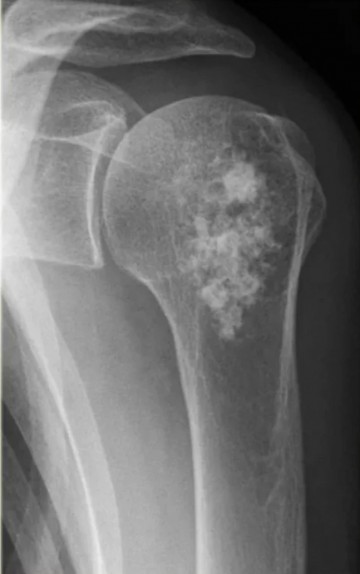

В основе инновационной разработки - радионуклид радий-223. Препарат «Ракурс, 223Ra» предназначен для лечения определённых видов онкологических заболеваний, преимущественно при метастазах в костях.

Радиоактивное излучение 223Ra целенаправленно воздействует на костные метастазы, уменьшая болевой синдром и улучшая качество жизни пациентов.